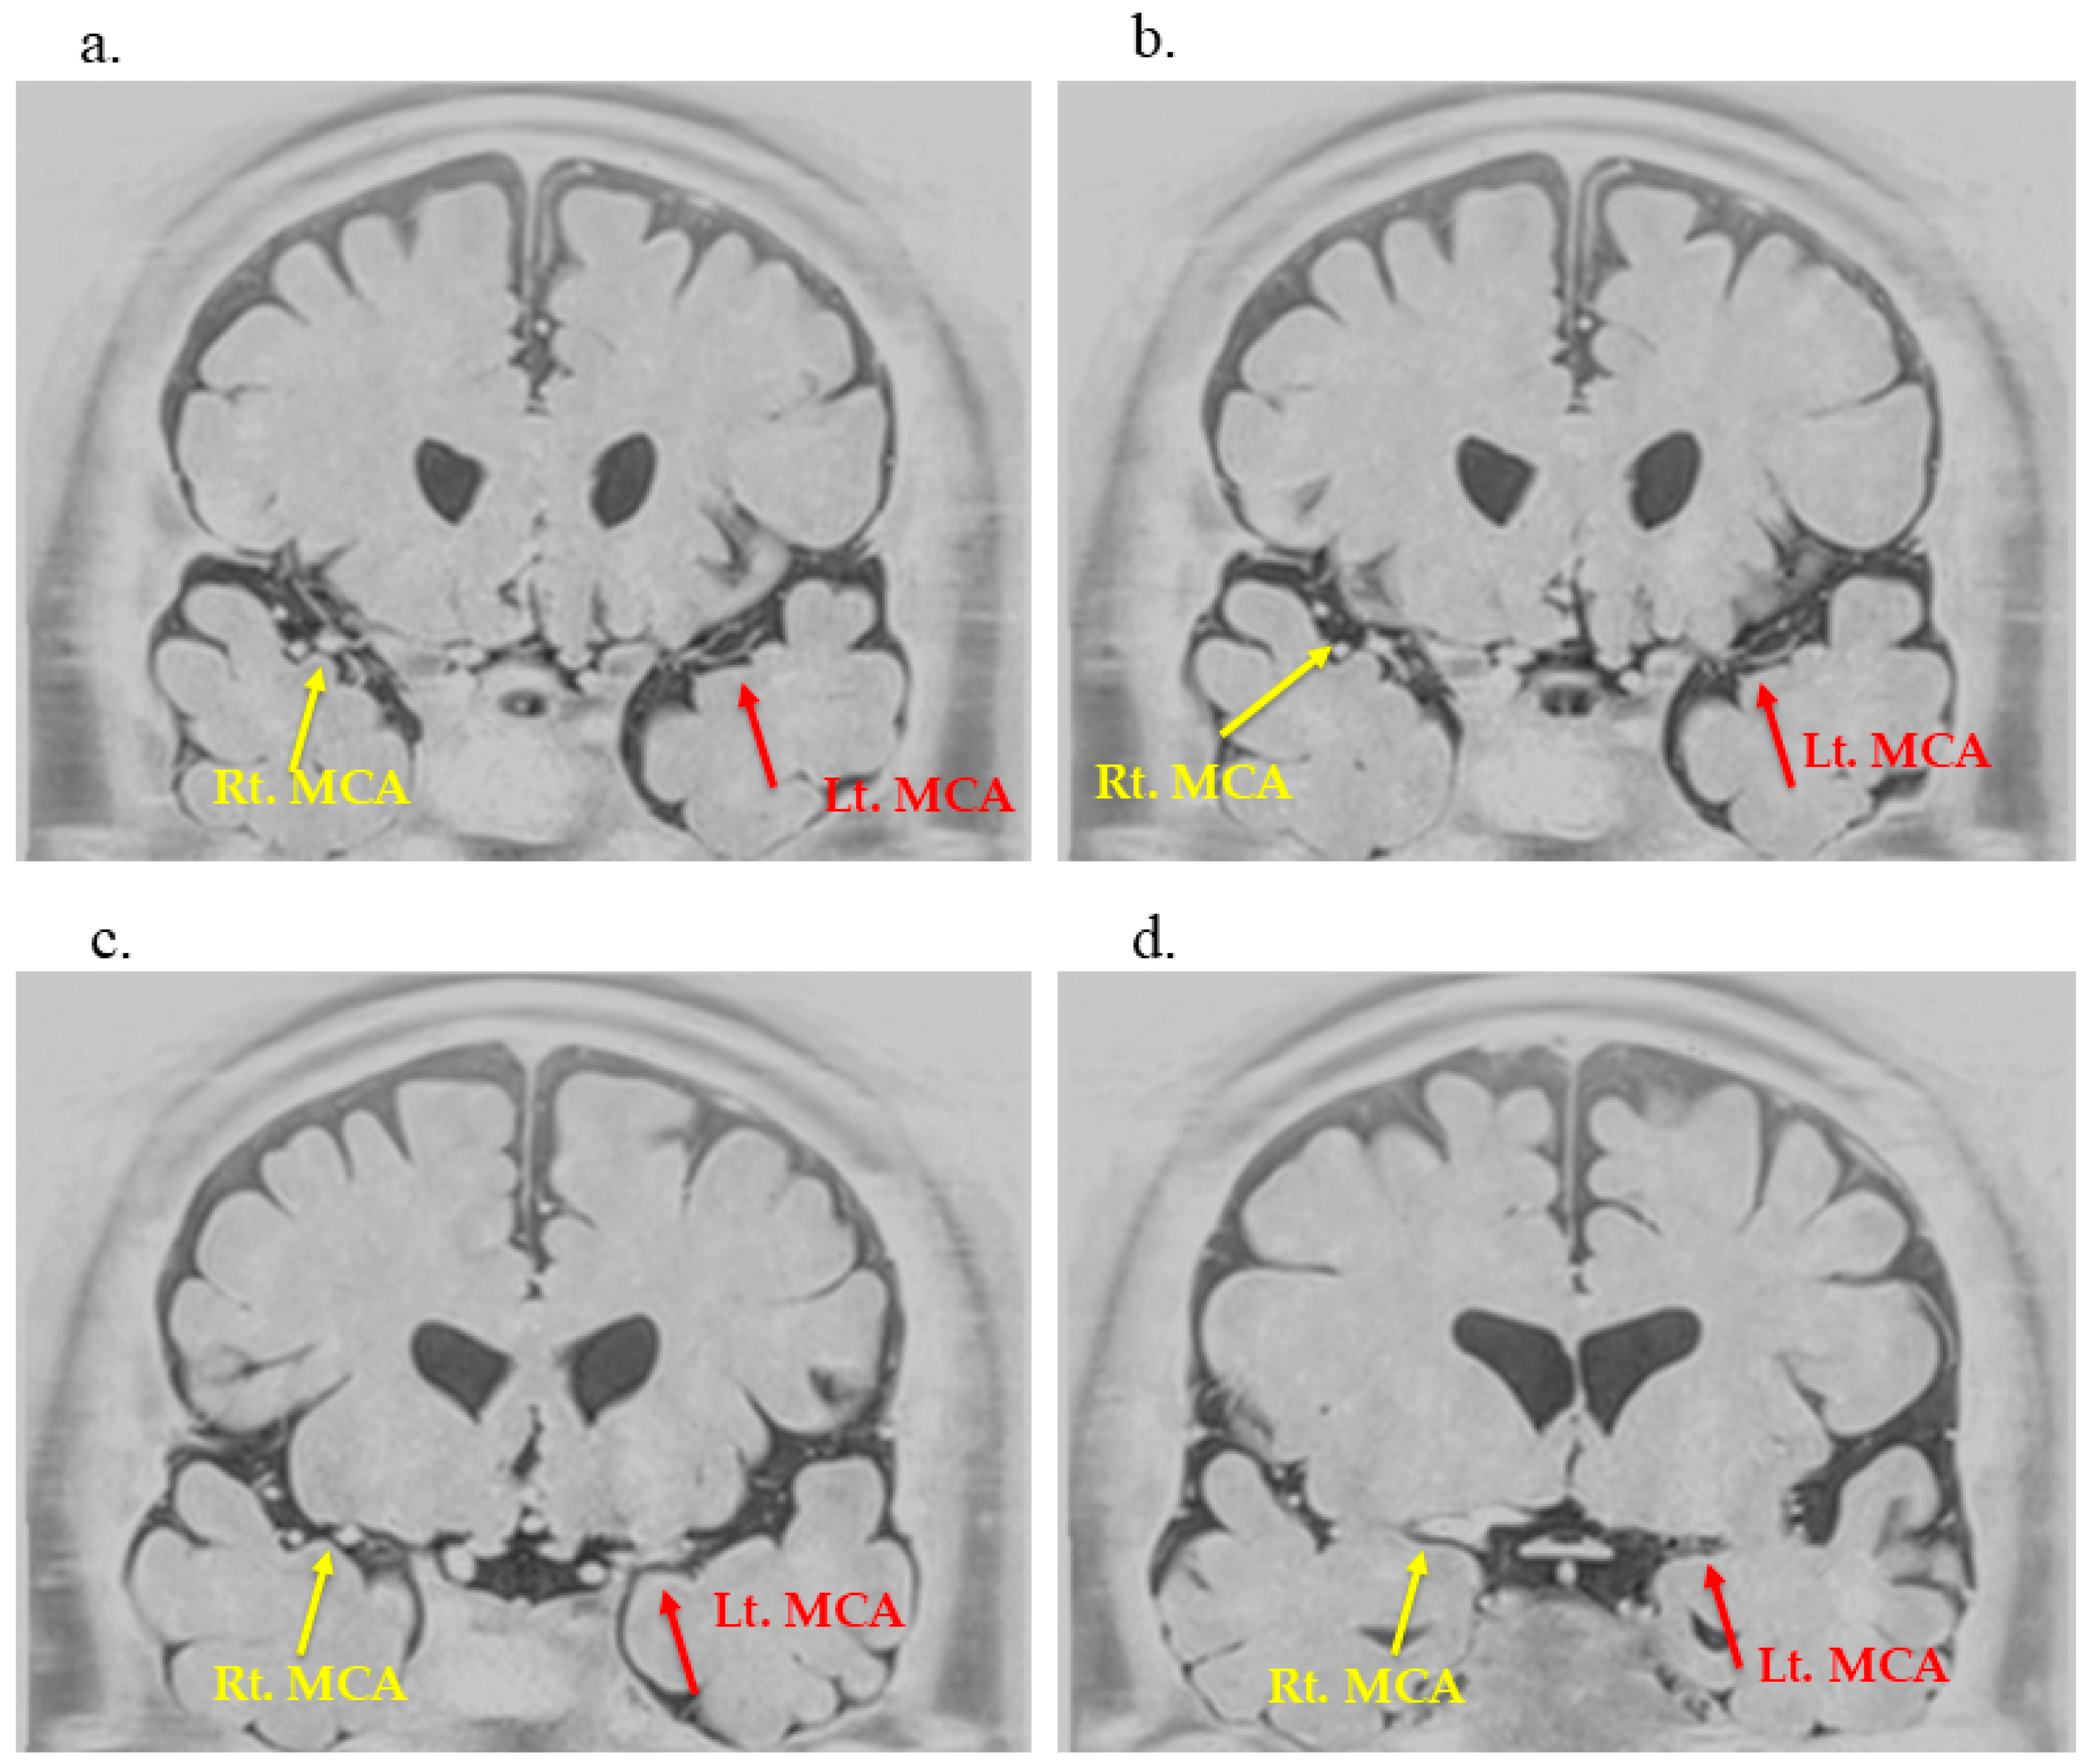

2. Case Description

3.3. Utility of BPAS in Detecting Moyamoya-like Vascular Changes